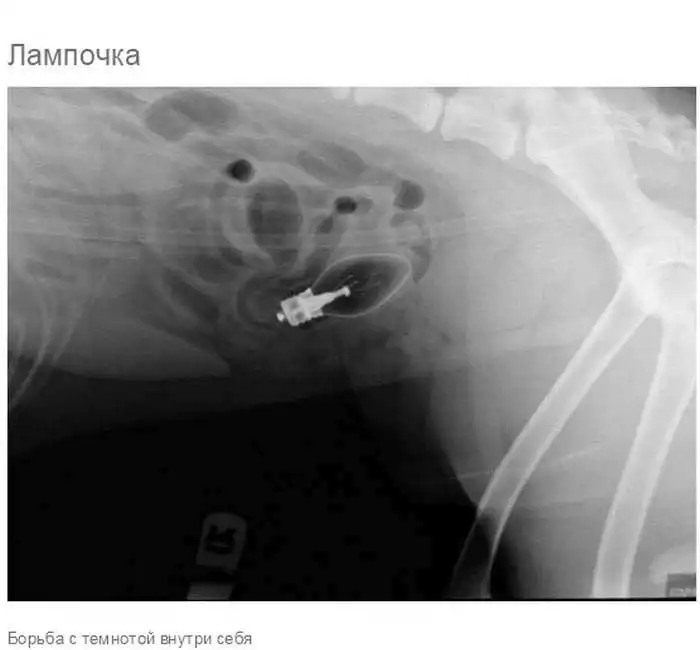

Что может оказаться в желудке собаки

Думаю, всем собачникам известно, что порой у собак бывают такие заскоки, когда они в прямом смысле слова жрут все подряд.